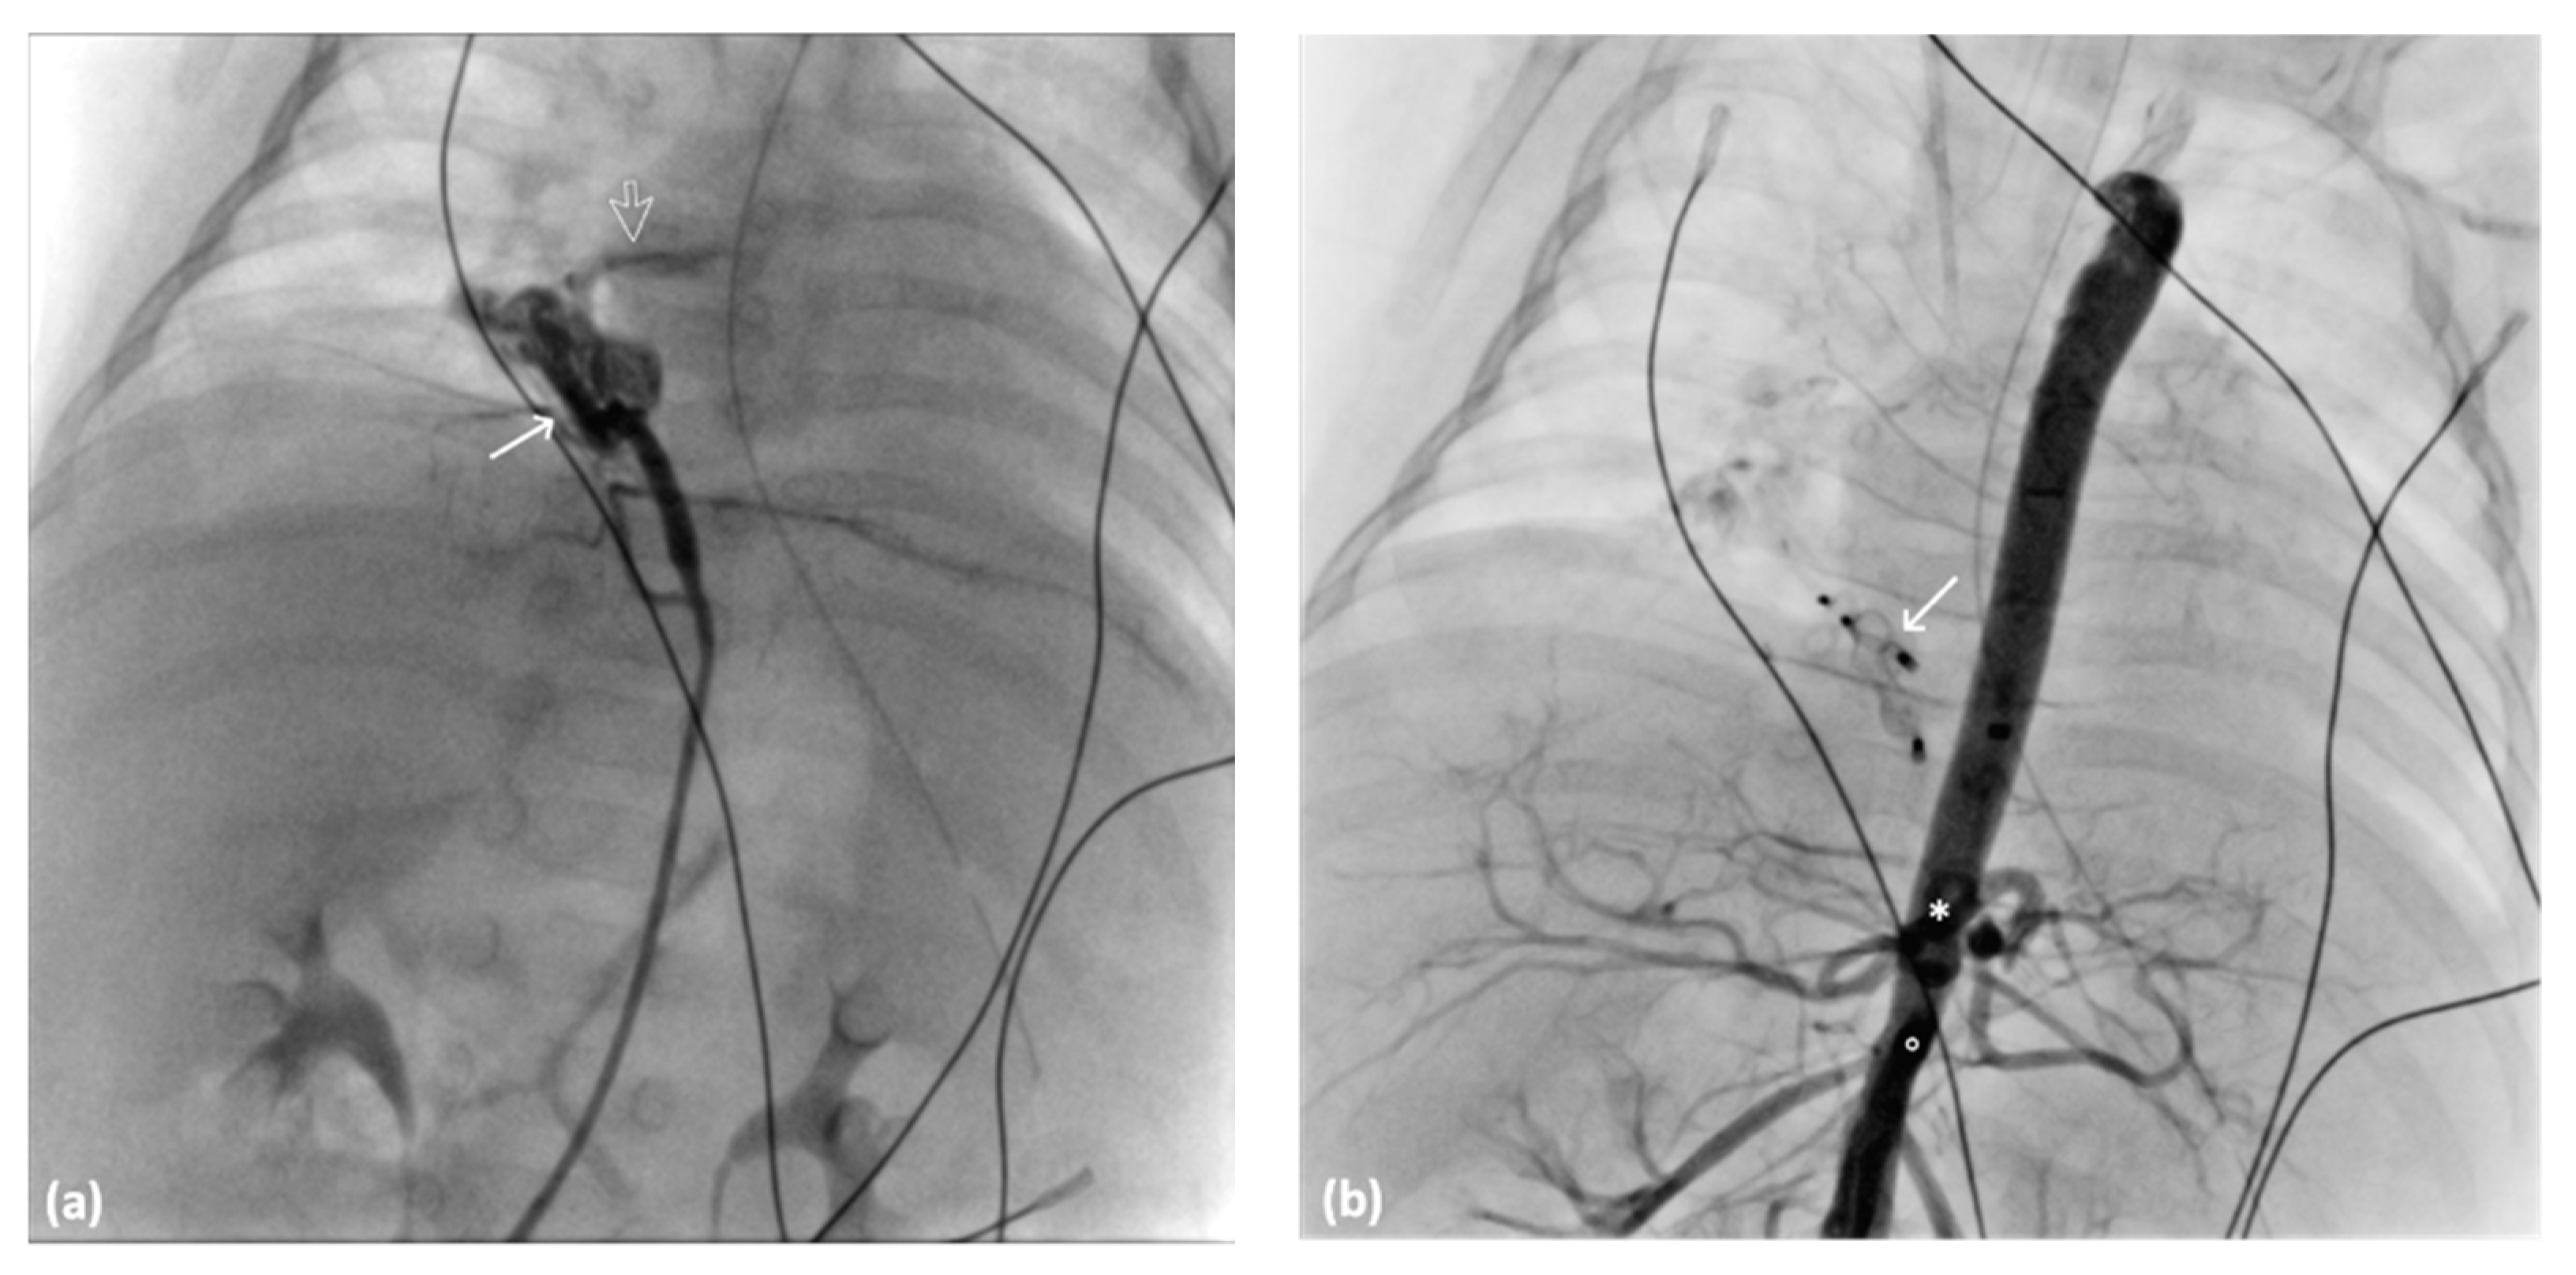

A 5-month-old full-term neonate experienced respiratory distress shortly after birth, with APGAR scores of 5 and 6 at 1 min and 5 min, respectively. Despite postintubation mechanical ventilatory support, the respiratory distress persisted. Cardiac sonography and chest CTA revealed an atrial septal defect and anomalous systemic arterial supply to the right lower lobe (Figure 5). The right lower lobe, posterior right upper lobe, and basal left lower lobe were affected by pneumonia. Cardiac catheterization was performed through the transfemoral approach by using a 4-Fr femoral sheath and catheter. Angiography revealed two engorged anomalous arteries originating from the abdominal aorta, forming a vessel sponge with rapid drainage into the pulmonary vein leading into the left atrium (Figure 6a). The anomalous arteries were embolized using 6 mm and 4 mm Amplatzer Vascular Plug II (AVP II; AGA Medical, Golden Valley, MN, USA) and a 4-Fr Judkins left catheter (Radifocus Optitorque, Terumo, Tokyo, Japan). After the deployment of the AVP, no residual shunt was observed (Figure 6b). Postembolization syndrome developed and subsided spontaneously. Although the respiratory condition initially improved after embolization, it later deteriorated due to respiratory failure arising from an uncontrollable lung infection. The patient succumbed to infection 2 months after embolization.

Figure 6.

Angiography images of 4-Fr Judking left catheter: (a) anomalous artery (arrow) creating a vessel sponge with pulmonary vein rapid drainage void (arrow) into the left atrium and (b) angiography image of the abdominal aorta after AVP II deployment (arrow) indicating no residual blood flow to the right lower lung. The ciliary trunk (*) and SMA (○) are presented.